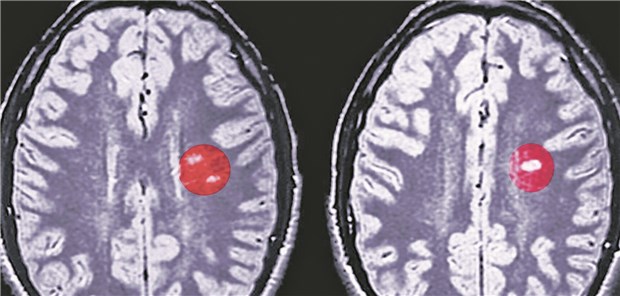

Hirnläsionen eines MS-Patienten im MRT-Bild: Neue Arzneien ermöglichen individuelle Therapien.

© Arteria Photography

Neurologenkongress

Neue MS-Medikamente für weniger Schübe und weniger Behinderung